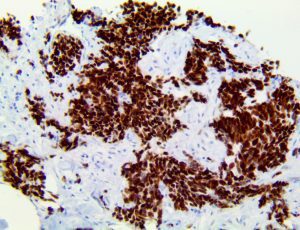

It is the ICU physician who is most likely to witness one of the deadliest manifestations of the abnormal immunological response, the cytokine storm syndrome (CSS). This response is also referred to by some as the cytokine release syndrome (CRS). CSS is characterized by continuous activation and expansion of macrophage and lymphocyte populations, which secrete large amounts of cytokines, causing the cytokine storm. This massive cytokine release is akin to hemophagocytic lymphohistiocytosis (HLH) disease, a syndrome characterized by initial unchecked and persistent activation of cytotoxic T lymphocytes and NK cells.

Clinical and laboratory manifestations of HLH include fever, enlarged liver and/or spleen, neurologic dysfunction, coagulopathy, liver dysfunction, cytopenias (i.e., low levels of erythrocytes, leukocytes, and/or platelets), hypertriglyceridemia, hyperferritinemia, hemophagocytosis, and eventually diminished NK cell activity as the immune system becomes progressively paralyzed. HLH can be familial (primary HLH) or secondary to another disease process (sHLH), such as rheumatic disease, in which it is referred to as macrophage activation syndrome (MAS, characterized by elevated ferritin).